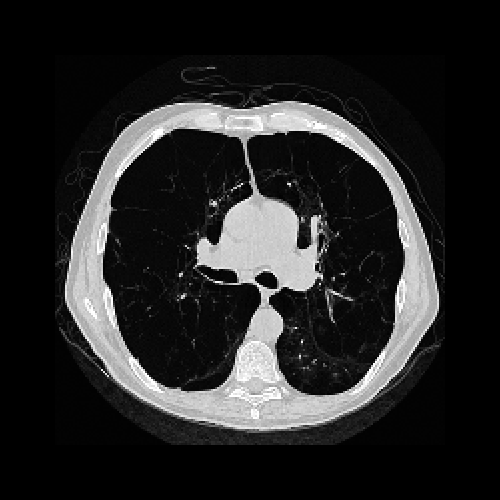

To assess the performance of the HLSF, four phantoms with structural patterns of different complexity have been considered (Fig. 4). PH-1 in Fig. 4(a) is the segmentation of a reconstructed slice of mouse lung tissue at micrometer scale. PH-2 in Fig. 4(b) is a multilevel segmentation of a MRI scan of a human brain. PH-3 in Fig. 4(c) is a multilevel segmentation of a CT slice of a human lung. PH-4 is the well-known Shepp-Logan phantom [16].

Refer to caption

(a) PH-1

(b) PH-2

(c) PH-3

(d) PH-4

Figure 4: Set of simulated data used to benchmark the HLSF. PH-1 has 784 ×\times 784 pixels; PH-2 has 592 ×\times 592 pixels; PH-3 has 500 ×\times 500 pixels; PH-4 has 512 ×\times 512 pixels.